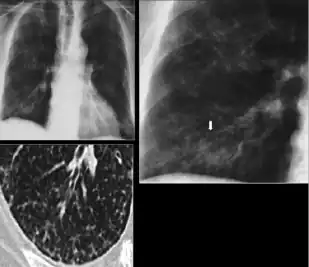

Chest X-ray of a person with advanced tuberculosis: Infection in both lungs is marked by white arrow-heads, and the formation of a cavity is marked by black arrows.

3. Nodule with poorly defined margins - Round density within the lung parenchyma, also called a tuberculoma. Nodules included in this category are those with margins that are indistinct or poorly defined (tree-in-bud sign[3]). The surrounding haziness can be either subtle or readily apparent and suggests coexisting airspace consolidation.

-

Chest x-ray showing nodule with margins that are indistinct or poorly defined (tree-in-bud sign) in post-primary pulmonary TB.